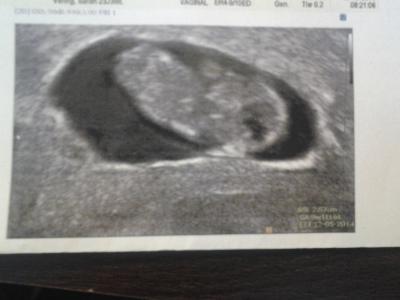

War heute morgen schon beim arzt gewesen weil ich den verdacht auf ne Pilz Infektion hatte, die sich leider auch bestätigt hat. Naja jedenfalls wurde dann direkt die komplette VU gemacht, so das ich nächste woche nicht wieder hin muss. Umd es war alles supi, der Wurm ist prima gewachsen und Herzchen hat geblubbert. Der Wurm ist jetzt 2, 57 cm groß und laut US bei 9+1ssw aber im MuPa steht trotzdem 9+2 , naja der eine Tag ist ja nicht schlimm. Ach ich bin Happy.

Bild zu Schon heute beim Arzt gewesen ... - Forum für Mai - Mamis